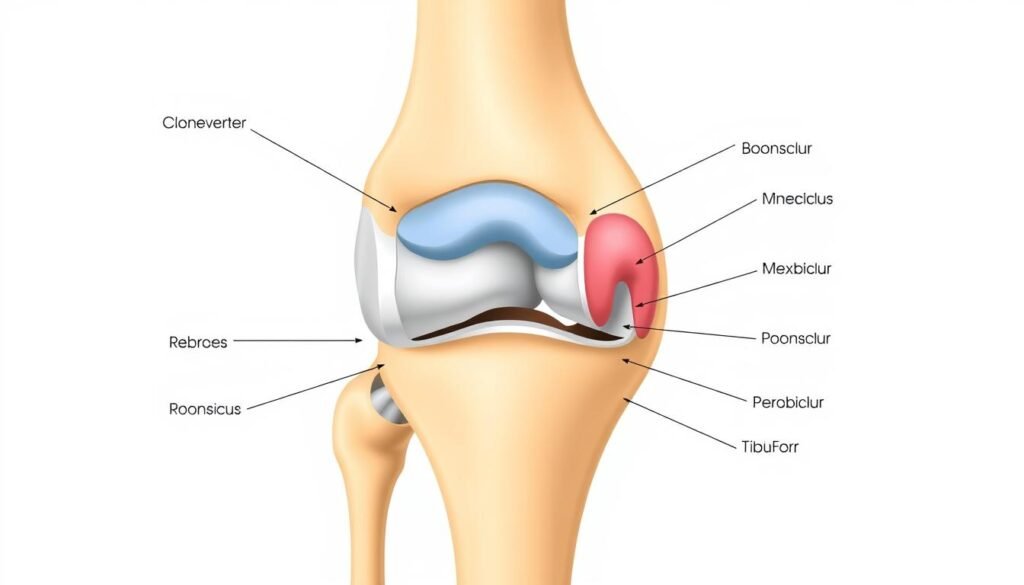

Bei der Knie-Totalendoprothese (K-TEP) werden alle Gelenkflächen des Kniegelenks ersetzt. Dies umfasst sowohl die femorale (oberschenkelseitige) als auch die tibiale (schienbeinseitige) Komponente. Die Oberschenkelkomponente besteht aus Metall und ahmt die natürliche Form der Femurkondylen (Oberschenkelrollen) nach. Die Schienbeinkomponente besteht aus einer Metallplatte mit einem Polyethylen-Inlay als Gleitfläche. In manchen Fällen wird auch die Rückfläche der Kniescheibe (Patella) durch eine Kunststoffkomponente ersetzt.

Man unterscheidet zwischen ungekoppelten und gekoppelten Vollprothesen:

- Ungekoppelte Prothesen: Die Stabilität wird durch die körpereigenen Bänder gewährleistet. Sie erlauben neben Beugung und Streckung auch eine gewisse Rotation im Kniegelenk.

- Gekoppelte Prothesen: Die Prothesenkomponenten sind mechanisch miteinander verbunden, was mehr Stabilität bietet, aber die Beweglichkeit einschränkt. Sie kommen zum Einsatz, wenn der Bandapparat stark geschädigt ist.